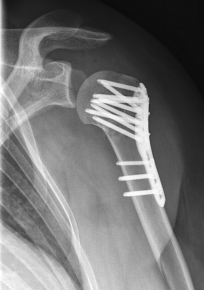

Proximaler Oberarmbruch5Proximaler Oberarmbruch6

Picture: Here is a subcapital upper arm break in a young woman. An angle stable plate osteosynthesis was performed to stabilize the head in correct position to the humeral shaft and shoulder joint. Especially in young patients, We strive to treat non-invasively and as gently as possible. This possibility is often due to the bone quality in young as opposed to older people.